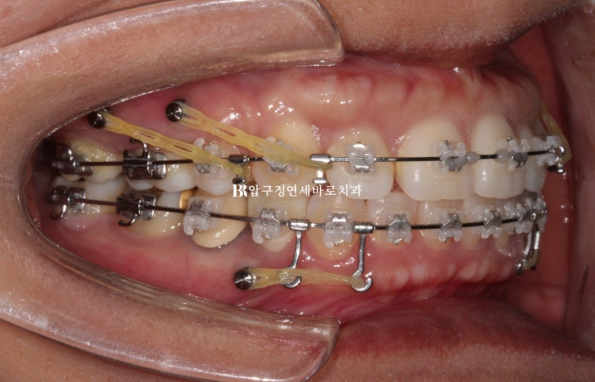

클리피씨로 치료하기로 하고 미니스크류를 위에 4개 아래 2개 총 6개를 식립하고 치료를 진행했습니다.

아래는 전체 치열을 뒤로 밀고 위에는 전체치열을 뒤로도 밀고 위로도 밀어올립니다.

22.09~24.04